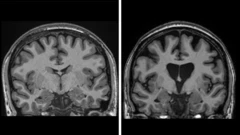

Os dados demonstram que, três anos após a cirurgia, houve, em média, 75% de redução da velocidade de avanço da doença, com base em uma medição que combina a cognição, funções motoras e a capacidade de se autogerenciar no dia a dia.

Os dados também demonstram que o tratamento está salvando as células cerebrais.

Os níveis de neurofilamentos no fluido espinhal (um claro sinal da morte de células do cérebro) deveriam ter aumentado em um terço, se a doença continuasse a progredir. Mas, na verdade, eles são inferiores aos do início do teste.